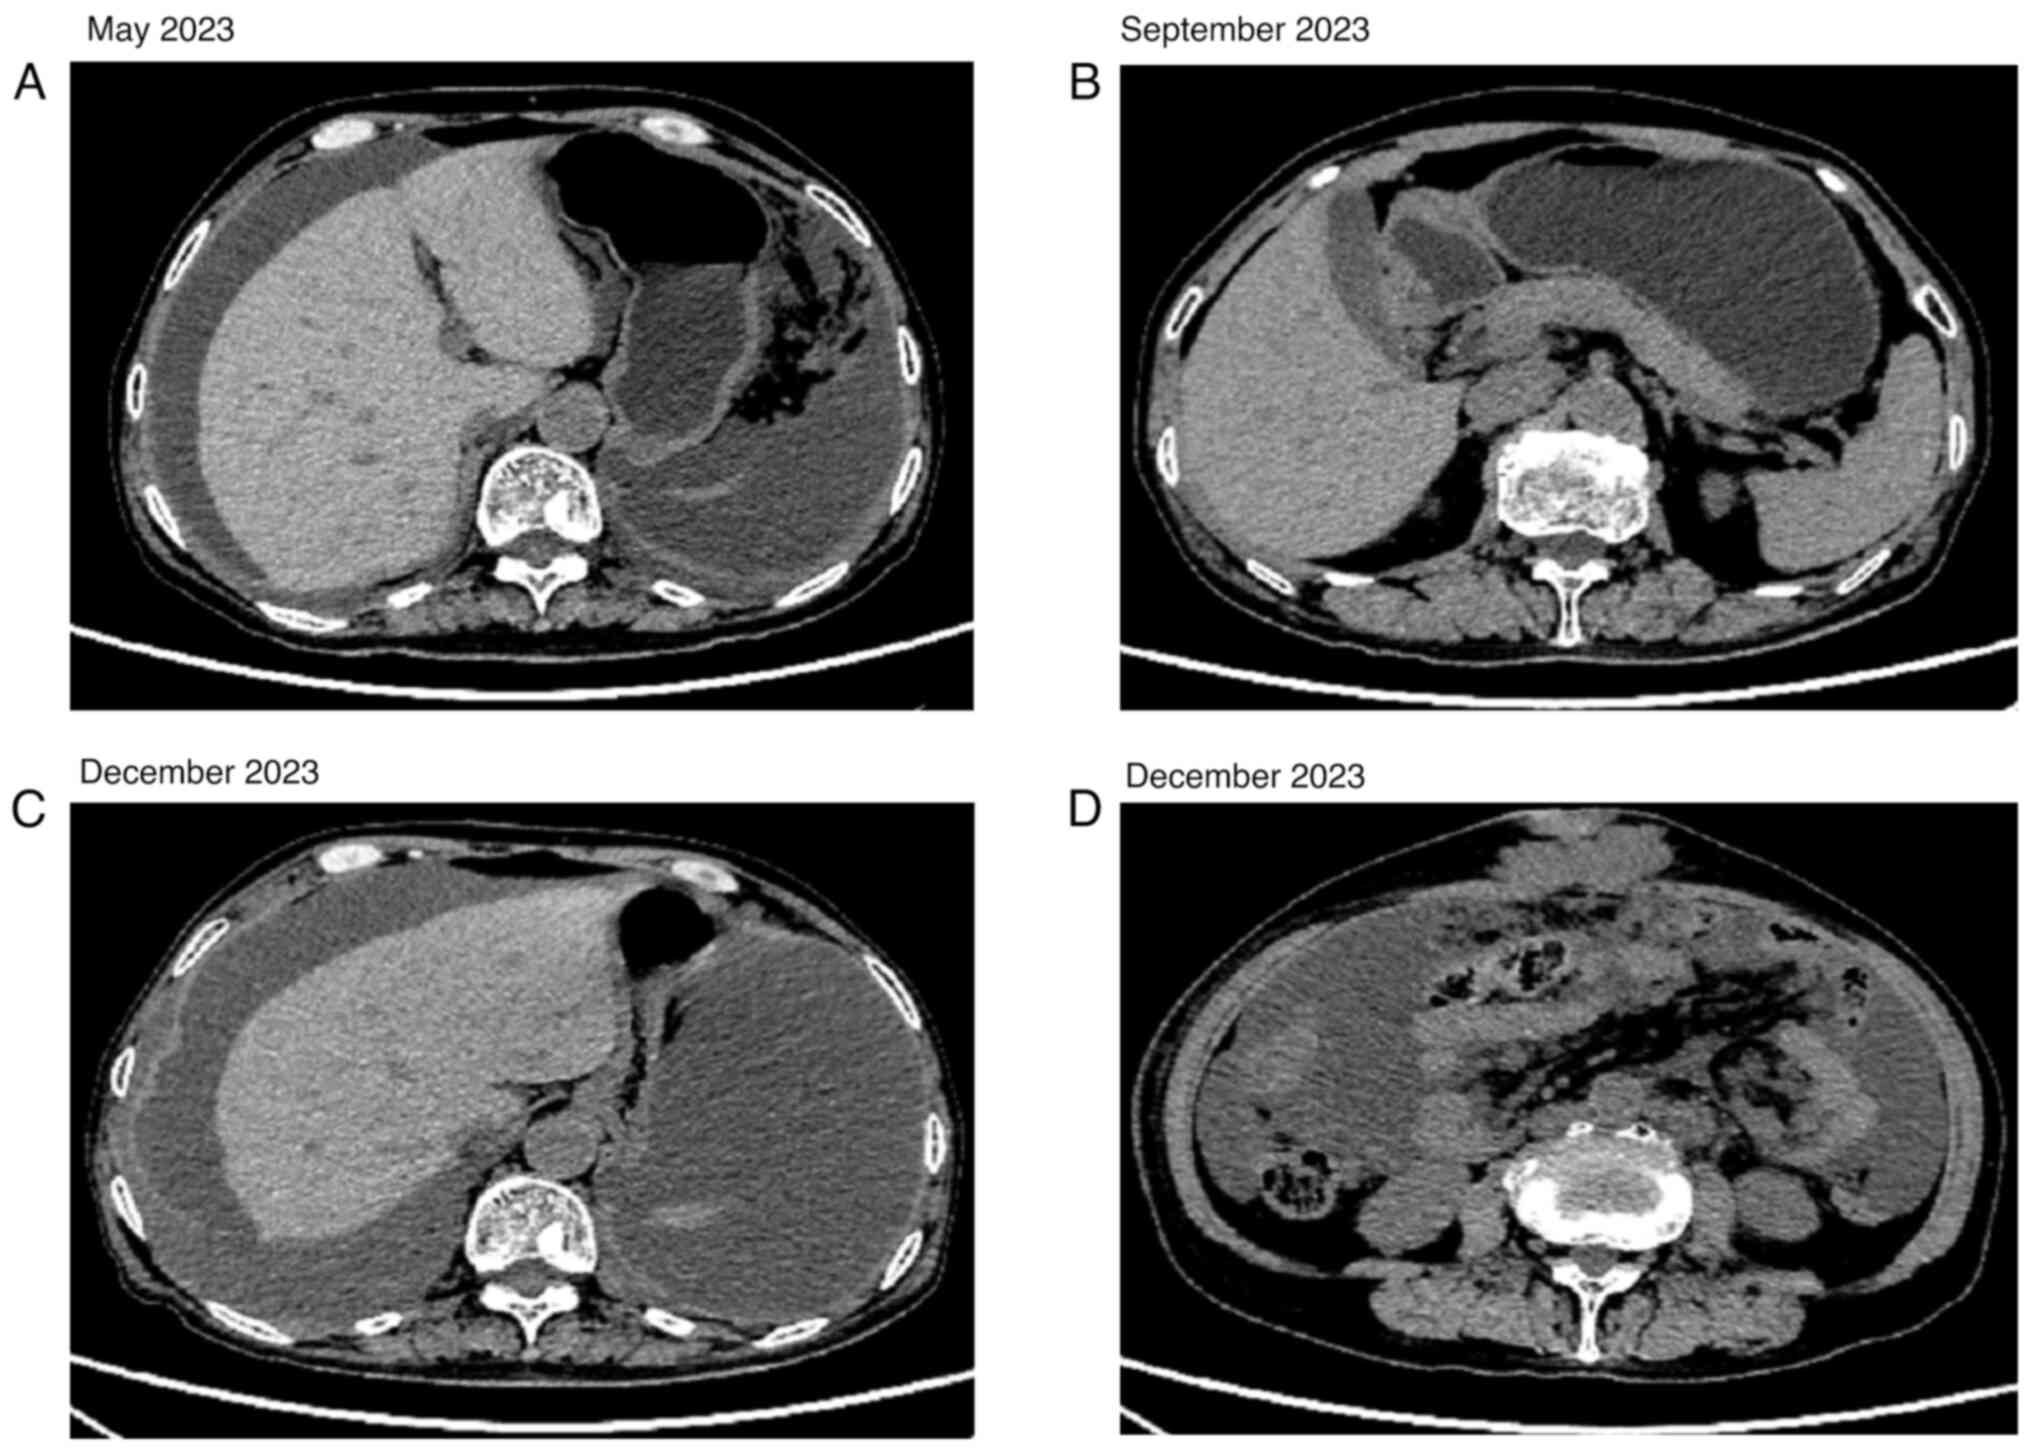

SMARCA4‑deficient uterine adnexal tumor with ascites: A case report and literature review

SWI/SNF‑related matrix‑associated actin‑dependent regulator of chromatin subfamily A member 4 (SMARCA4)‑deficient tumors are rare and highly aggressive tumors characterized by a loss of SMARCA4 expression, and SMARCA4‑deficient tumors in the adnexal area of the uterus are particularly rare. The present study describes the case of a 64‑year‑old woman who was admitted to Weifang People's Hospital (Weifang, China) with abdominal distension, and was observed to have a mass with ascites in the adnexal area of the uterus. Based on clinical, imaging and pathological findings, the patient was diagnosed with a SMARCA4‑deficient adnexal tumor with ascites. Biopsy of the left and right adnexal lesions was performed, and the patient was administered chemotherapy. After one cycle of bevacizumab, sindilizumab and carboplatin, no further treatment was administered. After biopsy and chemotherapy, the abdominal distension was alleviated and the general condition of the patient was satisfactory. The patient was followed up and died 3 months after treatment. Notably, it is important to avoid misdiagnosing this tumor as other types of adnexal uterine tumors, and morphological and immunohistochemical features may be useful for diagnosing primary SMARCA4‑deficient tumors in the adnexal area of the uterus.

Figure 1